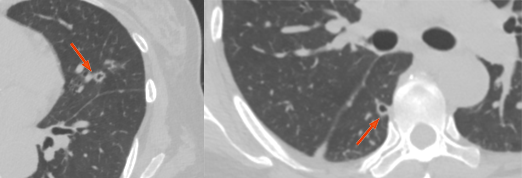

图片

直肠癌术后 2 年,发现右肺结节 1 周。双肺仅见 1 枚结节,穿刺活检证实为直肠癌转移。